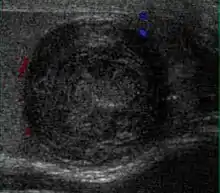

Fig. 3. Seminoma. (a) Seminoma usually presents as a homogeneous hypoechoic nodule confined within the tunica albuginea. (b) Sonography shows a large heterogeneous mass occupying nearly the whole testis but still confined within the tunica albuginea, it is rare for seminoma to invade to peritesticular structures.

Approximately 95% of malignant testicular tumors are germ cell tumors, of which seminoma is the most common. It accounts for 35%–50% of all germ cell tumors. Seminomas occur in a slightly older age group when compared with other nonseminomatous tumor, with a peak incidence in the fourth and fifth decades. They are less aggressive than other testicular tumors and usually confined within the tunica albuginea at presentation. Seminomas are associated with the best prognosis of the germ cell tumors because of their high sensitivity to radiation and chemotherapy.

Seminoma is the most common tumor type in cryptorchid testes. The risk of developing a seminoma is increased in patients with cryptorchidism, even after orchiopexy. There is an increased incidence of malignancy developing in the contralateral testis too, hence sonography is sometimes used to screen for an occult tumor in the remaining testis. On US images, seminomas are generally uniformly hypoechoic, larger tumors may be more heterogeneous [Fig. 3]. Seminomas are usually confined by the tunica albuginea and rarely extend to peritesticular structures. Lymphatic spread to retroperitoneal lymph nodes and hematogenous metastases to lung, brain, or both are evident in about 25% of patients at the time of presentation.